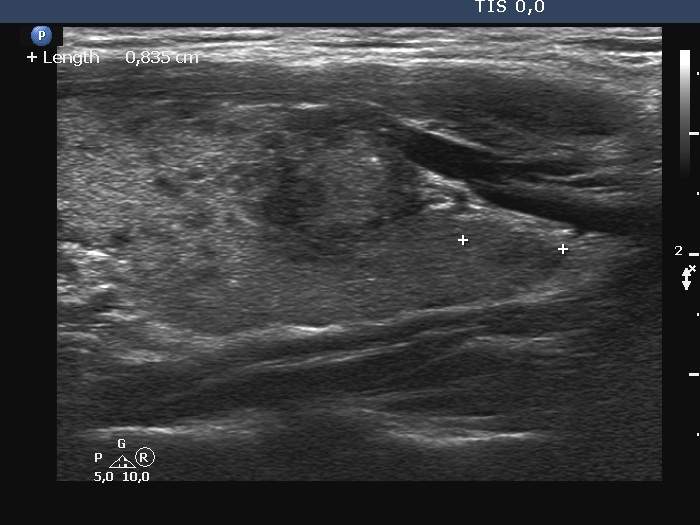

100 consecutive cases of papillary cancer - case 099 (ultrasonographic picture 7)

Left lobe, longitudinal scan. Due to technical reasons, the nodule is darker in longitudinal scan. Note a microcalcification.